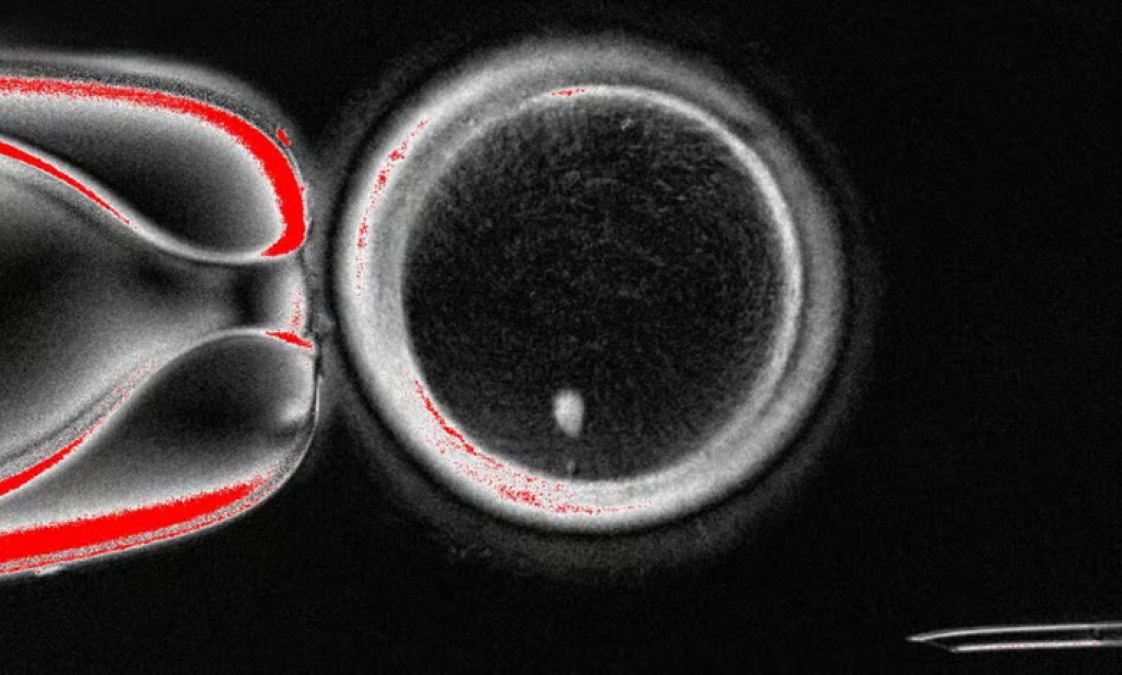

El equipo obtuvo óvulos de donantes y les extraía el núcleo. Después incorporaron núcleos de células cutáneas cultivadas, que aportaban los 46 cromosomas habituales. El reto era reducir esa carga genética a 23 cromosomas, el número correcto para que un óvulo pueda fusionarse con un espermatozoide.

La innovación consistió en manipular la división celular para inducir lo que llamaron “mitomeiosis”. Con esta técnica, núcleos destinados a dividirse por mitosis se vieron obligados a comportarse como si realizaran meiosis, produciendo la mitad de cromosomas. En total, el equipo produjo 82 óvulos reconstruidos y tras su fertilización, cinco alcanzaron la etapa de blastocisto, un paso inicial del desarrollo embrionario.